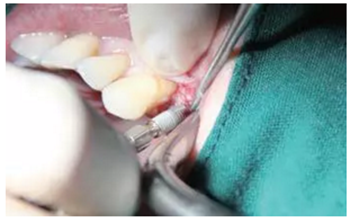

翻瓣與植入種植體

注意翻瓣不能太大,只需將窩洞頂端及周邊充分暴露即可。檢查種植窩洞頂端邊緣的骨壁情況,將窩洞頂端的高點去除,防止其干涉愈合基臺的就位。植入種植體植入時通過扭力扳手來確定最終的植入扭力,并判斷是否合適放置愈合基臺,也可以通過松動度測量儀測量ISQ值來判斷。

圖4 小翻瓣暴露窩洞頂端并去除高點